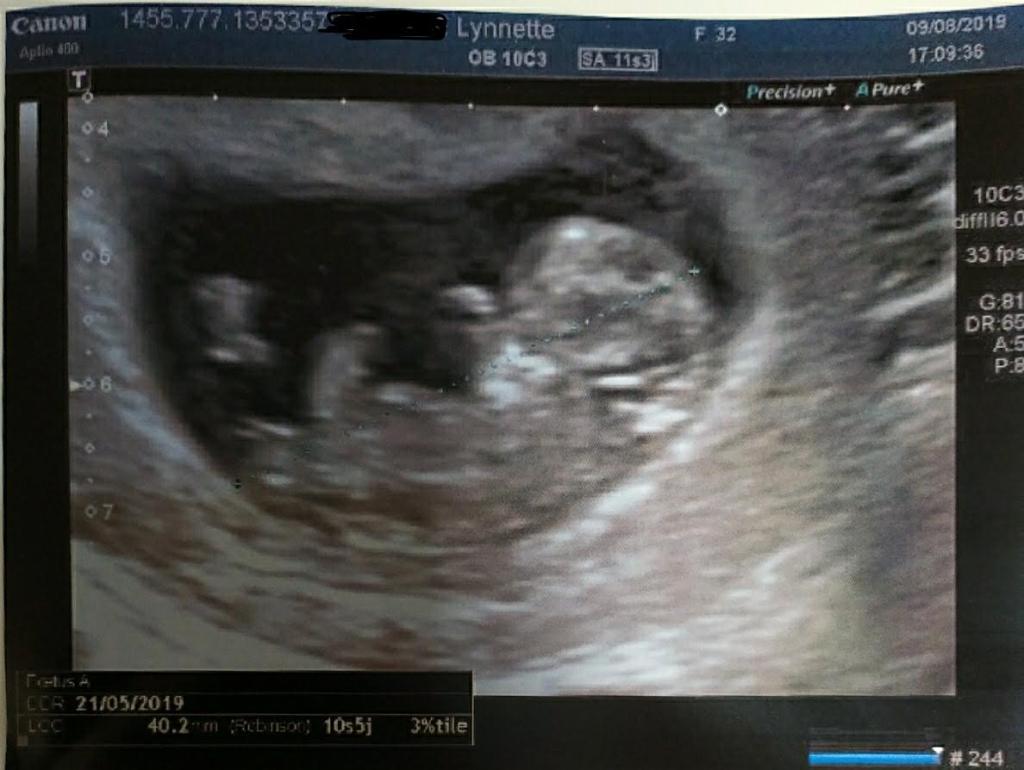

So here is baby O at 10w3d.

I was measuring at 10 weeks 3 days which is about two days ahead of what my app Nurture calculated.

They do things a little different here in France and have me another set of measurements which is considered theoretical 11 weeks 4 days. From what I understand they add a week or two from the last menstrual date because predicting when implantation occurred is just not possible unless you did IVF.